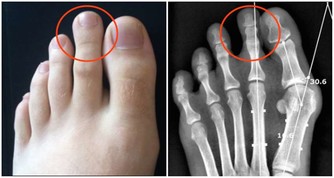

足癬是一種接觸傳染性皮膚病。如果接觸了帶真菌的腳、鞋襪、拖鞋、毛巾和水等,真菌數量比較多,毒力比較強,接觸者的皮膚又比較潮濕,就容易被傳染。

例如,商場試衣間裡的試裝鞋、健身房的公共拖鞋、足療中心的拖鞋和設備等,都是感染腳氣的重要途徑。